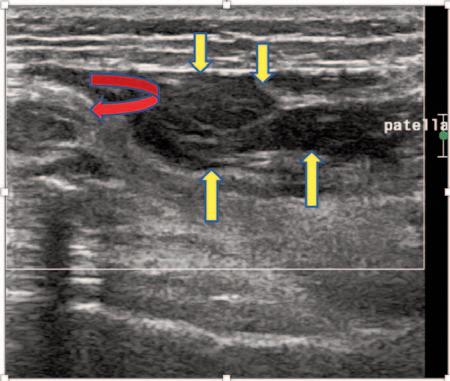

The Use of MSK Ultrasound with Quadriceps Muscle Injury.

Manske R, Voight M, Wolfe C, Page P.